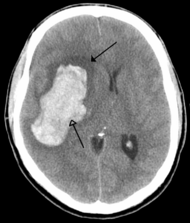

Brain tumours can be either benign or cancerous. Most malignant tumours arise from another part of the body, most commonly from the lung, breast and skin.[176] Cancers of brain tissue can also occur, and originate from any tissue in and around the brain. Meningioma, cancer of the meninges around the brain, is more common than cancers of brain tissue.[176] Cancers within the brain may cause symptoms related to their size or position, with symptoms including headache and nausea, or the gradual development of focal symptoms such as gradual difficulty seeing, swallowing, talking, or as a change of mood.[176] Cancers are in general investigated through the use of CT scans and MRI scans. A variety of other tests including blood tests and lumbar puncture may be used to investigate for the cause of the cancer and evaluate the type and stage of the cancer.[176] The corticosteroid dexamethasone is often given to decrease the swelling of brain tissue around a tumour. Surgery may be considered, however given the complex nature of many tumours or based on tumour stage or type, radiotherapy or chemotherapy may be considered more suitable.[176]

Most strokes result from loss of blood supply, typically because of an embolus, rupture of a fatty plaque causing thrombus, or narrowing of small arteries. Strokes can also result from bleeding within the brain.[191] Transient ischaemic attacks (TIAs) are strokes in which symptoms resolve within 24 hours.[191] Investigation into the stroke will involve a medical examination (including a neurological examination) and the taking of a medical history, focusing on the duration of the symptoms and risk factors (including high blood pressure, atrial fibrillation, and smoking).[192] Further investigation is needed in younger patients.[193] An ECG and biotelemetry may be conducted to identify atrial fibrillation; an ultrasound can investigate narrowing of the carotid arteries; an echocardiogram can be used to look for clots within the heart, diseases of the heart valves or the presence of a patent foramen ovale.[193] Blood tests are routinely done as part of the workup including diabetes tests and a lipid profile.[193]

Some treatments for stroke are time-critical. These include clot dissolution or surgical removal of a clot for ischaemic strokes, and decompression for haemorrhagic strokes.[194][195] As stroke is time critical,[196] hospitals and even pre-hospital care of stroke involves expedited investigations – usually a CT scan to investigate for a haemorrhagic stroke and a CT or MR angiogram to evaluate arteries that supply the brain.[193] MRI scans, not as widely available, may be able to demonstrate the affected area of the brain more accurately, particularly with ischaemic stroke.[193]